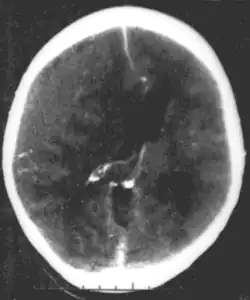

O hematoma epidural acontece quando a hemorragia ocorre entre a membrana externa rígida que reveste o cérebro (dura-máter) e o crânio.[1] Muitas vezes, há perda de consciência após um traumatismo craniano, uma breve recuperação e, em seguida, uma nova perda de consciência.[2] Outros sintomas podem incluir cefaleia, confusão, náusea e paralisia.[3] Complicações podem incluir convulsões.[3]

A causa é tipicamente uma contusão na cabeça que resulta na fratura do osso temporal e hemorragia da artéria meníngea média.[1] Ocasionalmente, pode ocorrer devido a uma coagulopatia ou malformação vascular.[3] O diagnóstico geralmente é feito por tomografia computadorizada ou ressonância magnética.[3] Quando esta condição ocorre na coluna, é chamada de hematoma epidural espinhal.[1]